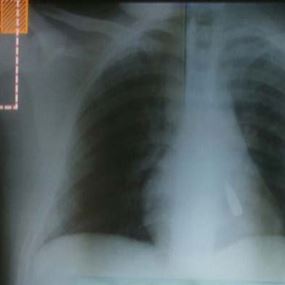

تستقر رصاصة ابتهاج "بلدية" طائشة الى جانب قلب حسين احمد عذب ( 15 عاما)، و"يستقر" الطفل بين الحياة الموت منذ ليل امس في مستشفى الرسول الاعظم بعد تعليمات وزير الصحة للعامة وائل ابو فاعور بعلاجه على نفقة الوزارة.